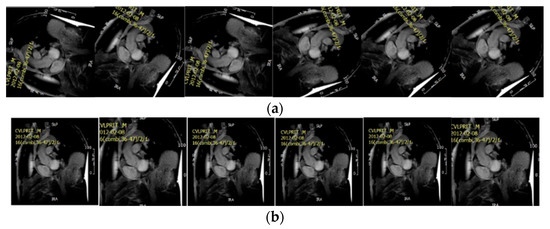

2. Materials

4.1. Data Preparation

4.4. Segmentation Result Based on State of Art Methods